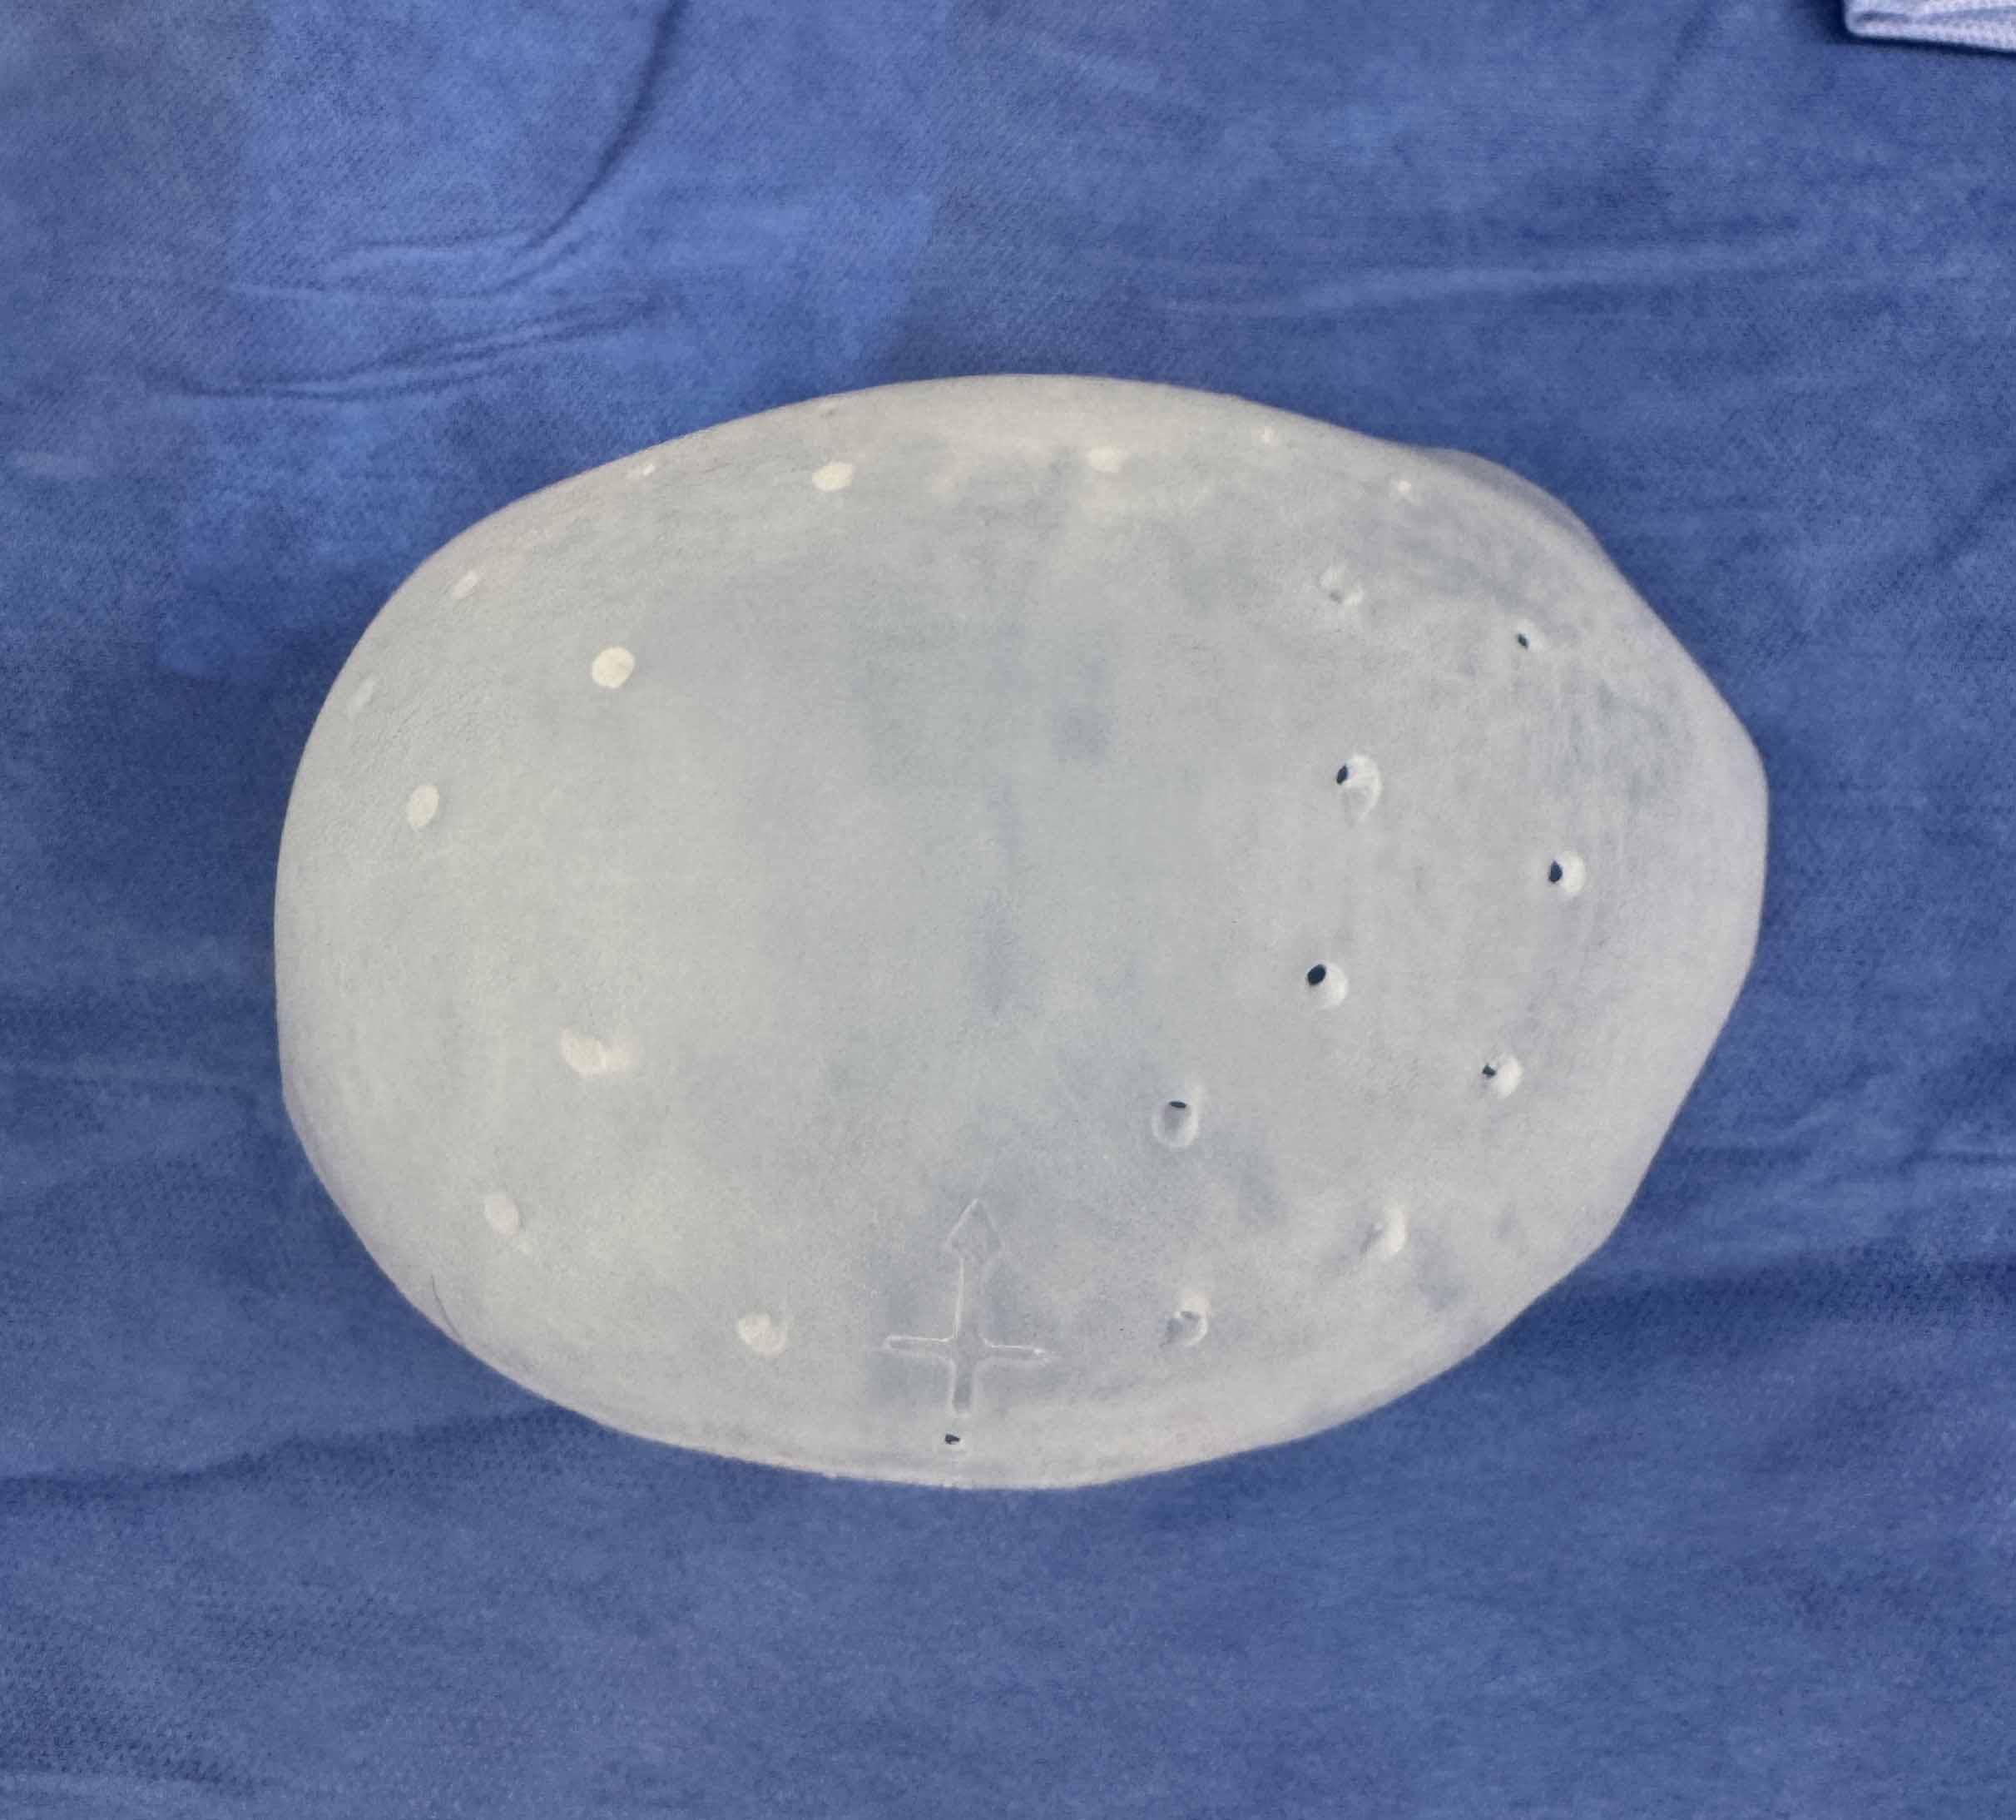

Desire for further skull augmentation after a primary skull implant.

Five years after an initial custom skull implant placement a new custom skull implant that increased the volume by 35% was placed.

Desire for further skull augmentation after a primary skull implant.

Five years after an initial custom skull implant placement a new custom skull implant that increased the volume by 35% was placed.